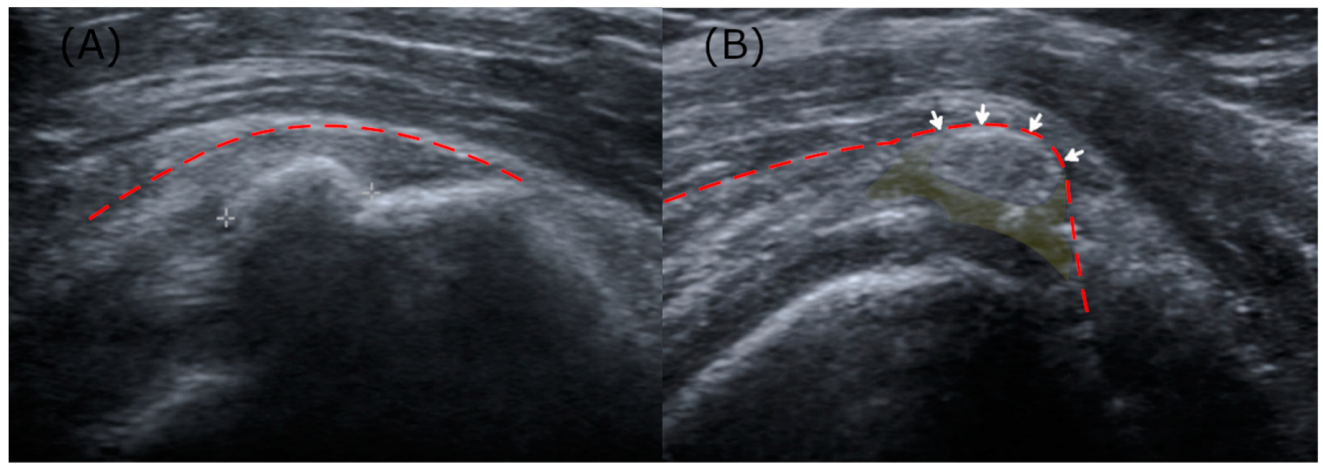

Key ultrasonographic parameters encompassed Sconfienza’s classification, shadow faintness, bursal wall contact, and peri-calcific hypoattenuation. Sconfienza’s classification, which grades echogenicity within calcification, was used to grade the deposits as either Grade I (hyperechoic and hard) or Grade II/III (homogeneous and soft/hypoechoic and fluid-like) [5,19]. Shadow faintness was defined as the presence of either partial or complete obscuration of the acoustic shadow. Bursal wall contact was marked by the displacement of the smooth bursal wall by calcific deposits, and peri-calcific hypoattenuation was defined by hypoattenuation of the tendon tissues around the deposits (Figure 2). In the analyses concerning the ultrasound parameters, cases without a shoulder ultrasound performed within a one-month window were excluded. The ultrasonographic parameters were evaluated by a physiatrist with over 10 years of experience in musculoskeletal practice. The evaluations were performed independently, without prior knowledge of the radiographic analysis results.

Figure 2.

(A) An arc-shaped calcification (Sconfienza Grade 1) with acoustic shadowing, lacking both bursal contact and peri-calcific effusion. (B) A hypoechoic calcification (Sconfienza Grade 3), where the acoustic shadow is diminished, accompanied by bursal wall contact and peri-calcific tendon effusion. The bursal wall, representing the inferior boundary of the subdeltoid–subacromial bursa, is delineated with a dotted red line; areas where calcific deposits contact the bursa are indicated by arrows; peri-calcific hypoattenuation regions are highlighted in yellow.